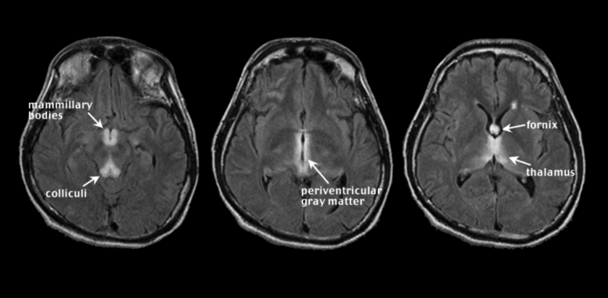

WE occurs with chronic alcoholism and thiamine deficiency. If untreated, WE patients can develop KS, a severe neurological disorder characterized by anterograde amnesia (Harper 2006; Zahr et al. 2011). Malnutrition, vomiting, and diarrhea are common in chronic alcoholism and can contribute to thiamine deficiency (Fields et al. 1994; Gloria et al. 1997; Morgan 1982; Ross et al. 2012). Further, the gastrointestinal tract’s ability to absorb necessary quantities of thiamine is diminished in alcoholics (Hoyumpa 1980; Thomson 2000), and the liver, which houses a large part of the body’s supplies of thiamine, may not be able to store thiamine in the same capacity if it is in a diseased state (Butterworth 2009; Levy et al. 2002). Classical clinical signs of WE included visual, gait, and mental disturbances (Victor et al. 1971), but more recent assessments describe mild, moderate, and severe signs and symptoms including anorexia, loss of memory, and emotional changes (Thomson et al. 2008). An MRI image of acute WE (see figure 2) has symmetrical bright spots, or hyperintensities, clearly visible on T2-weighted images, and those created by fluid attenuation inversion recovery2 (FLAIR). The bright spots appear in the midbrain gray matter surrounding the cerebral aqueduct (i.e., periaqueductal gray matter), mammillary bodies, and tissue surrounding the third ventricle3 (Lenz et al. 2002; Sullivan and Pfefferbaum 2009). These findings agree with postmortem diagnosis of WE, often requiring evidence of lesions in the mammillary bodies and periventricular areas (e.g., Caine et al. 1997). In addition, observed MR hyperintense areas in WE include the thalamus, cerebellar vermis (Murata et al. 2001), dorsal medulla, tectal plates (Ha et al. 2012), olivary bodies, and dorsal pons (Liou et al. 2012). MRI analysis of KS patients compared with unaffected research participants (i.e., nonalcoholic control subjects) revealed substantial volume shrinkage of the mammillary bodies in KS and a lesser but significant volume deficit in uncomplicated alcoholics (Sheedy et al. 1999; Sullivan et al. 1999b; but see Shear et al. 1996; Victor et al. 1989). In contrast with early MR studies suggesting that KS affects the mammillary bodies while sparing the hippocampi (Squire et al. 1990), more recent work demonstrates hippocampal volume deficits in KS (Sullivan and Marsh 2003). Other regions affected by KS are the thalamus, orbitofrontal cortex (Jernigan et al. 1991b), cerebellum, and pons (Zahr et al. 2009).

2Researchers use different MRI techniques to highlight different aspects of the brain. Techniques mentioned in this article include T1 weighted, T2 weighted, and FLAIR.

3 The cerebral aqueduct and third ventricle are part of the brain’s ventricular system—a set of cavities in the brain that produce, transport, and remove cerebrospinal fluid. This system also includes the lateral ventricles and fourth ventricle.

Hepatic Encephalopathy (HE)

HE, occurring in acute or chronic liver disease, including acute liver failure and cirrhosis, is believed to arise, at least partially, from high levels of ammonia circulating in the blood. HE patients may appear confused and disoriented and have poor coordination (Prakash and Mullen 2010; Vaquero et al. 2003). T1-weighted images of HE show bilateral, symmetrical, and high-intensity signals in basal ganglia structures, particularly the globus pallidus and substantia nigra (Binesh et al. 2006; Cordoba et al. 2002; Naegele et al. 2000; Pujol et al. 1996; Taylor-Robinson et al. 1995) (see figure 3). T2-weighted FLAIR images show hyperintense signals along the corticospinal tract and diffuse increases in white-matter signal intensities in the cerebral hemispheres (Rovira et al. 2002, 2008). These in vivo MR features correspond with evidence of increased numbers of nonneuronal (i.e., glial) cells called astrocytes in basal ganglia and cerebral cortex of HE brains (Caine et al. 1997). Although discriminating features of WE and HE have been outlined, these diseases can be difficult to differentially diagnose and distinguish, because patients can appear to have similar symptoms and comparable MRI results, especially among alcoholics (Thorarinsson et al. 2011).